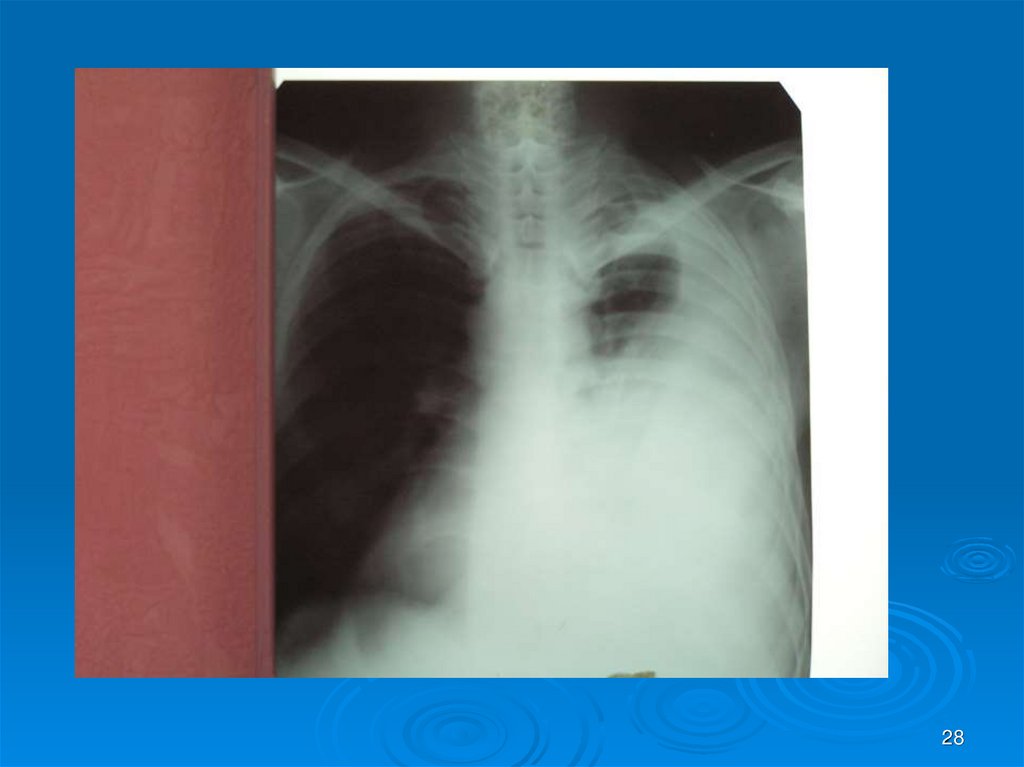

28.

28